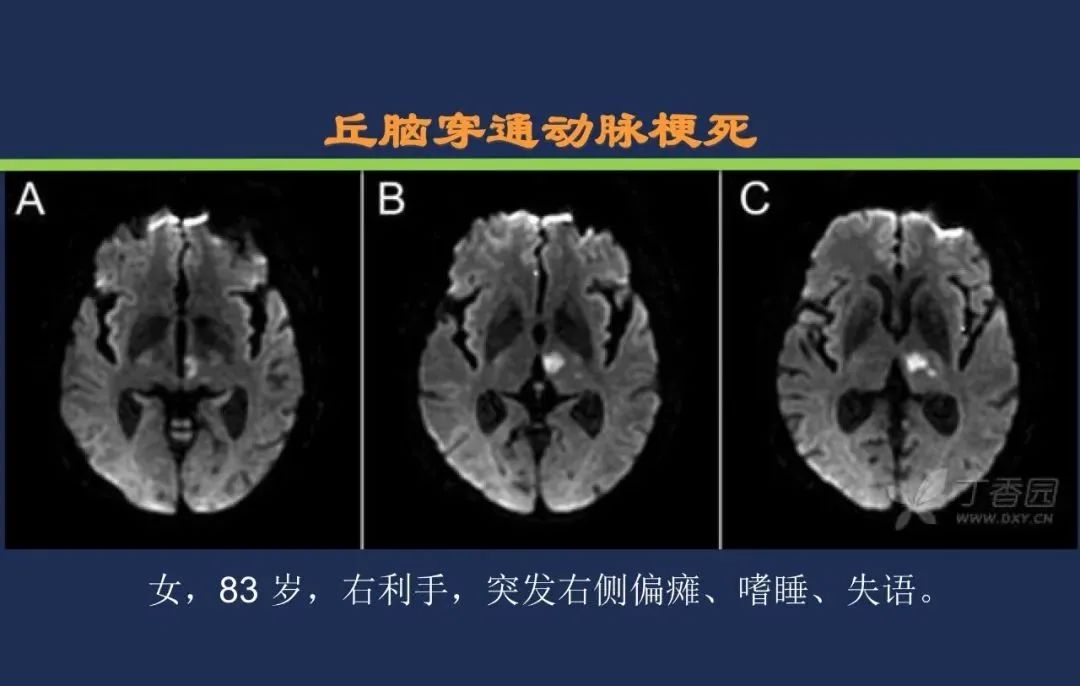

椎基底动脉梗死大脑后动脉丘脑穿通动脉-Percheron动脉